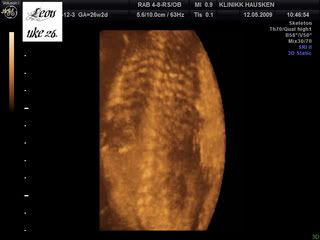

Og ryggraden:

Han ble målt til å være nesten 1100 gram allerede nå! Det betyr at han er 14 % over gjennomsnittet! Så legen på Hausken ville ha meg til glukosebelastningstest for å utelukke svangerskapsdiabetes[&:] Jeg er egentlig i høy risk for det, i og med at jeg har PCOS, var noe overvektig før graviditet, og jeg har diabetes type 2 i familien.